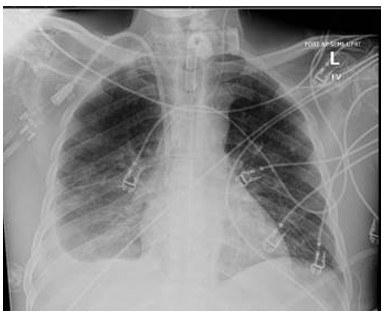

A 79-year-old male with a past medical history of Alzheimer’s dementia, chronic respiratory failure with tracheostomy and ventilator dependence, end stage renal disease, and atrial fibrillation is admitted to the intensive care unit from an outside hospital with septic shock. Urine cultures were positive for Vancomycin-resistant Enterococcus faecium and the tracheal aspirate was positive for Stenotrophomonas, Pseudomonas, and Proteus species. Chest x-ray demonstrated a right pleural effusion, which was present since outside hospital admission two and a half weeks prior. Decision was made to drainto rule out a source of persistent septic shock. Ultrasound guided thoracentesis was performed with ultrasound visualization during therapeutic aspiration. A total of 1400 cc of serous fluid was removed. After the procedure, the patient was briefly hypotensive, which resolved without intervention. Oxygenation remained stable. Pleural studies revealed a paucicellular lymphocytic transudate.